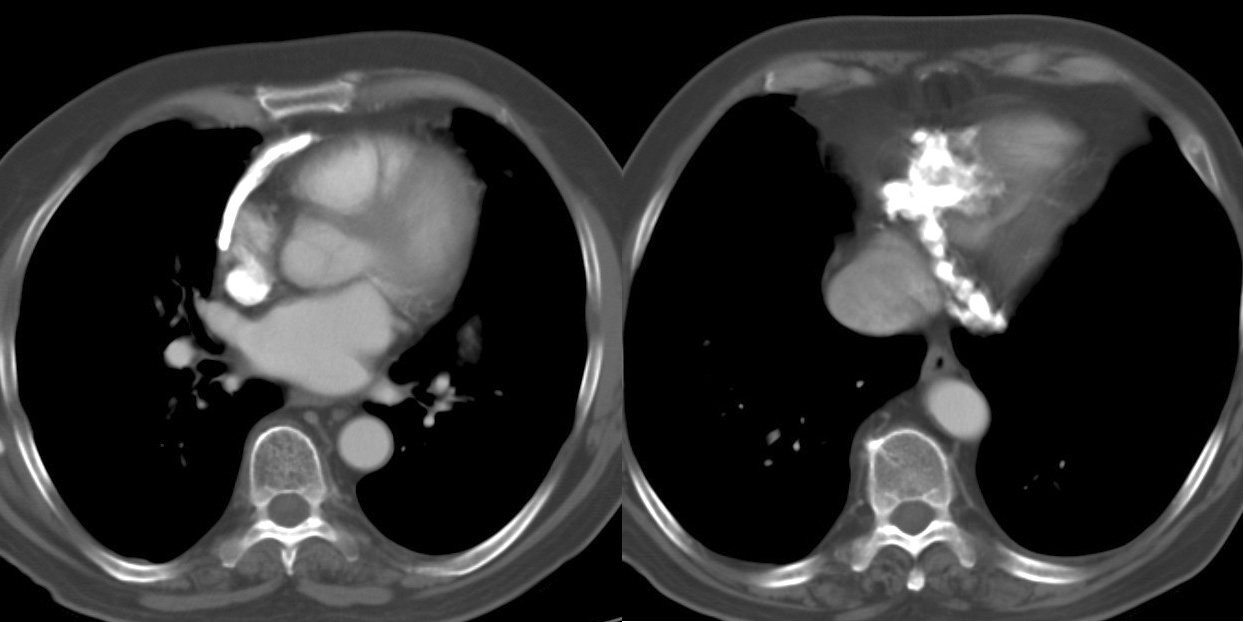

Case 2

Peric calcification